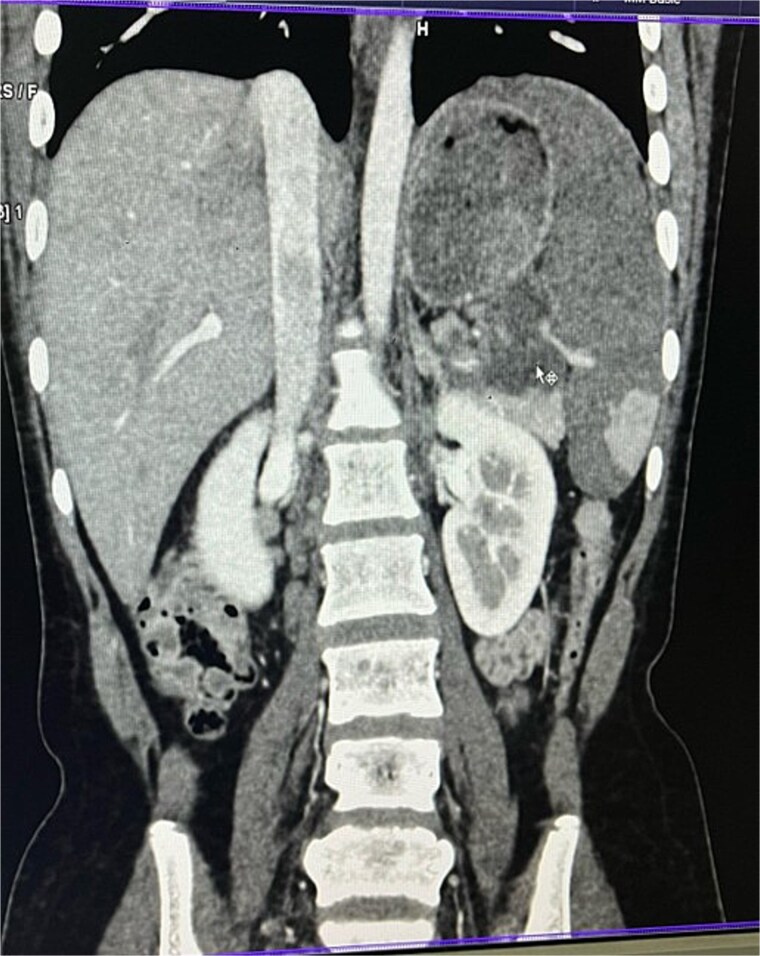

腹结核(TB)是一种罕见的肺外表现,累及胰腺和脾脏极为罕见,常被误诊为恶性肿瘤。我们提出的情况下,22岁的女性慢性胃痛,体重减轻,发烧。影像学显示胰腺尾部及脾门附近有坏死淋巴结肿块伴脾梗死。细针抽吸细胞学证实为结核病,患者对抗结核治疗反应良好,避免了手术干预。本病例强调了在流行地区的上腹部肿块鉴别诊断中考虑结核的重要性,以防止不必要的手术。

Abdominal tuberculosis (TB) is a rare extrapulmonary manifestation, with pancreatic and splenic involvement being extremely uncommon and often misdiagnosed as malignancy. We present the case of a 22-year-old female with chronic epigastric pain, weight loss, and fever. Imaging revealed a necrotic lymph node mass near the pancreatic tail and splenic hilum with splenic infarction. Fine-needle aspiration cytology confirmed TB, and the patient responded well to anti-tubercular therapy, avoiding surgical intervention. This case underscores the importance of considering TB in the differential diagnosis of upper abdominal masses in endemic regions to prevent unnecessary surgeries.